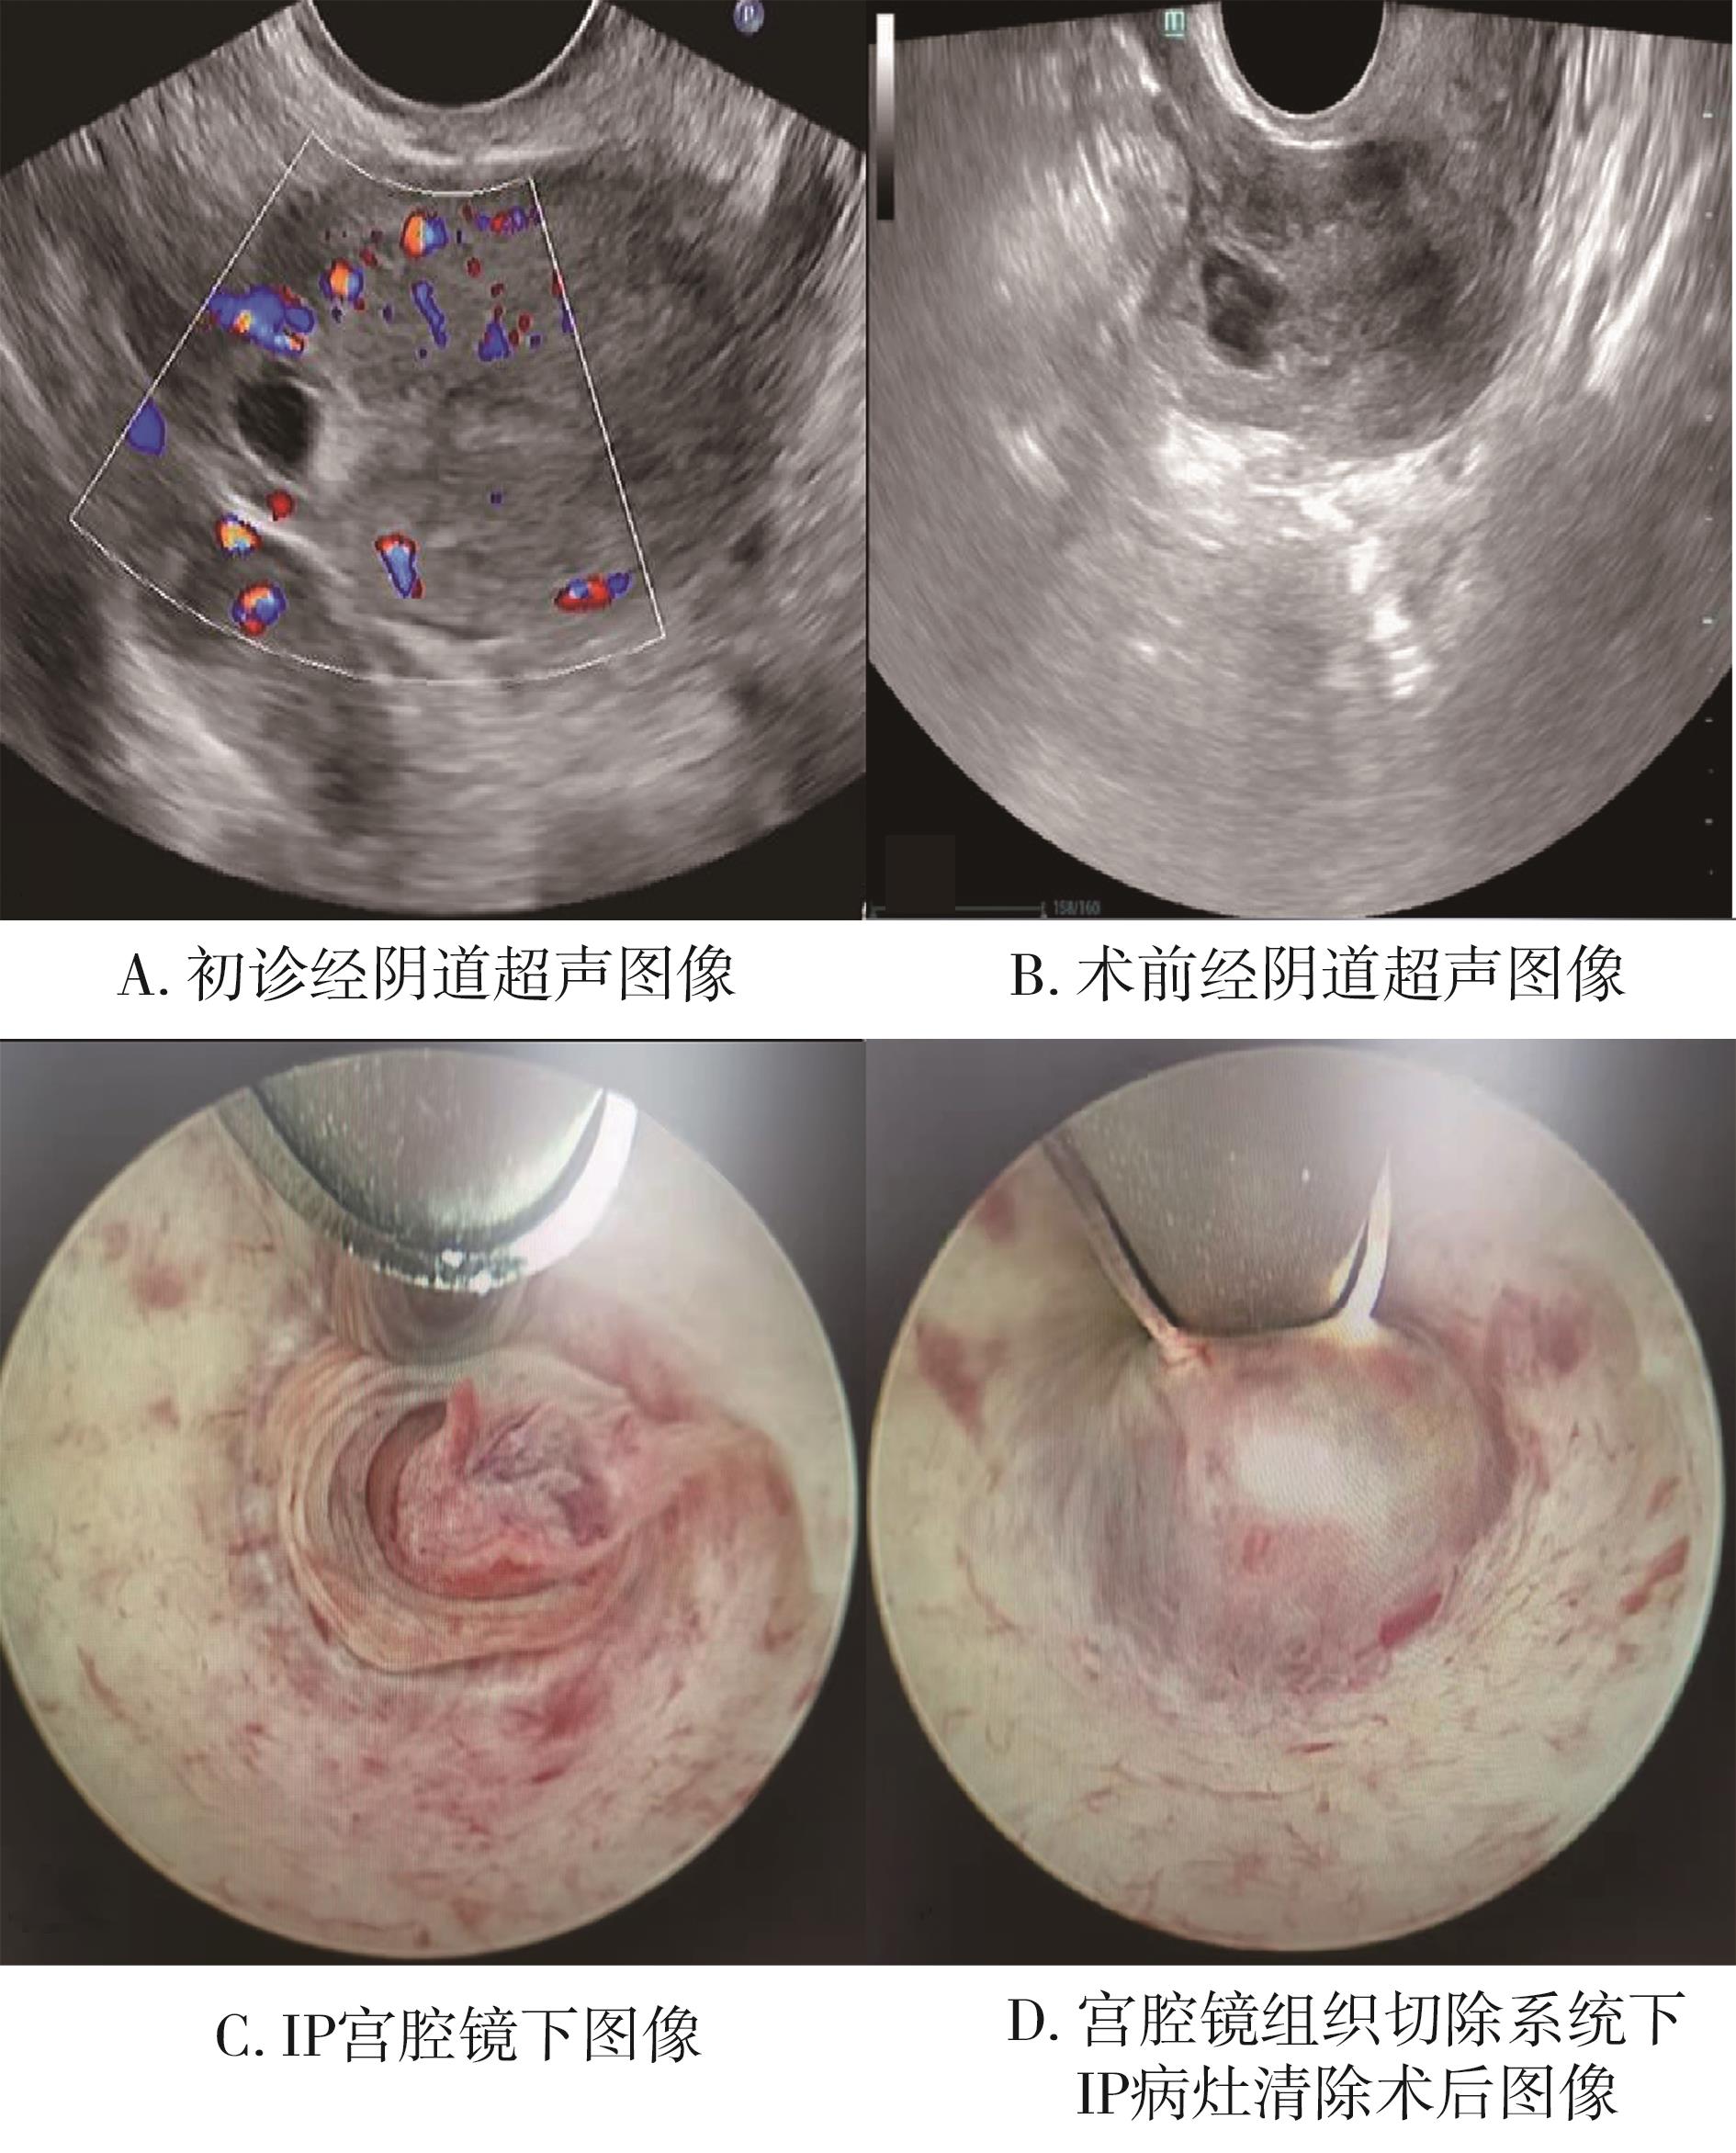

• 宫腔镜组织切除系统治疗输卵管间质部妊娠的可行性及安全性探索

2023, 48(7):816-819. DOI: 10.13406/j.cnki.cyxb.003267

摘要 (79) HTML (56) PDF 1.09 M (213) 评论 (0) 收藏

摘要:目的 探讨宫腔镜组织切除系统在输卵管间质部妊娠中治疗的可行性及安全性。方法 收集2019年4月至2022年4月江西省妇幼保健院妇科收治的采用宫腔镜组织切除系统治疗的16例未破裂型输卵管间质部妊娠患者的临床资料,回顾性分析患者的术前血β-人绒毛膜促性腺激素(beta-human chorionic gonadotropin,β-HCG)、B超情况、手术时间、术中出血量及术后血β-HCG正常时间等。结果 16例未破裂型输卵管间质部妊娠患者术前血β-HCG值为830~31 153 mIU/mL,平均(8 643.561±1 752.000) mIU/mL,B超下妊娠物最大为33 cm×28 cm,最小为11 cm×10 cm。均在检查镜下明确诊断为输卵管间质部妊娠,使用宫腔镜组织切除系统行间质部妊娠病灶清除术,其中2例中转腹腔镜,平均手术时间为34(20,92) min,平均术中出血量为46.6(10,250) mL,术程顺利,无明显并发症。术后平均住院时间2 d,血β-HCG恢复正常时间为(22.00±5.11) d,术后1个月复查B超均未见妊娠组织残留,术后半年随访过程中共5例患者成功受孕。结论 宫腔镜组织切除系统在未破裂型输卵管间质部妊娠治疗中可保留器官完整性。